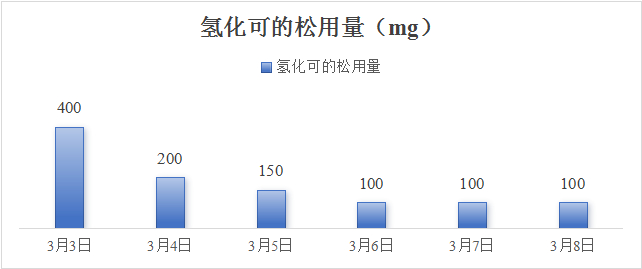

医嘱给予哌拉西林他唑巴坦抗感染,补液扩容、补充血钠,去甲肾上腺素2.7 μg/(kg·min)持续泵入,期间血压波动在78~100/51~69 mmHg之间。患者血压对去甲肾上腺素呈明显依赖,在补充1 000 mL胶体及1 700 mL晶体后,去甲肾上腺素一旦减量血压即降低到上述下界值。经补液后患者尿量维持250 mL/h。床旁超声可见下降静脉宽度由入院时的1.0 cm增加至1.9 cm。由于CT提示肾上腺占位,遂请内分泌科会诊, 考虑肾上腺占位伴肾上腺危象可能,遂完善腹部增强CT可见双侧肾上腺增大,不规则,伴少量钙化(图 2)。03-03晨8:00测血皮质醇14.96 ng/mL (52.7~224.5 ng/mL)、促肾上腺皮质激素1 096 ng/mL (≤ 46 ng/mL),加用氢化可的松200 mg快速静滴,随后200 mg静脉泵入维持24 h,2024-03-03日下午患者神志清楚,精神状态改善,恢复自主进食,血压逐渐上升并维持在130~140/60~85 mmHg,血钠130 mmol/L。03-04日,患者神志清楚,GCS评分15分,去甲肾上腺素减停,血压波动在125~130/58~86 mmHg左右,继续予以氢化可的松200 mg静脉泵入维持,当日下午转入内分泌病房继续治疗。住院期间氢化可的松用量情况见(图 6),03-09日停用氢化可的松后改为醋酸泼尼松片口服,日剂量为8:00 5 mg,16:00 2.5 mg。期间查T-spot阳性,抗核抗体谱、自身免疫性抗体、病毒学均阴性。出院诊断: 原发性肾上腺皮质功能不全,肾上腺危象。症状好转后于2024-03-13日出院,出院继续维持醋酸泼尼松片8:00 5 mg,口服,16:00 2.5 mg,口服用药方案。随访至今,患者一般情况良好,可从事简单体力劳动。

| 图 6 住院期间氢化可的松每日用量 |